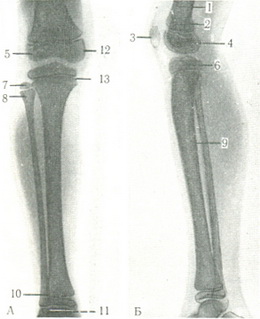

На знімках кісток нижніх кінцівок видна більш інтенсивна тінь кісткового речовини і легка тінь навколишніх м'яких тканин. Зовнішні контури компактної пластинки кістки рівні і чіткі. Внутрішня поверхню кортикального шару служить кордоном між компактним і губчастим кістковим речовиною і кістковомозкової порожнини. В області диафизов ця межа більш контрастне, в епіфізах і метафизах більш згладжена, в них видно дрібнопористі структура губчастого речовини. У дітей є ядра окостеніння і паросткові хрящові зони у вигляді вузької смужки з чіткими, але нерівними краями (рис. 96).

![]() |

96. Задній (А) і лівий (Б) знімки кісток правої гомілки юнаки. 1 - діафіз стегнової кістки; 2 - метафиз стегнової кістки; 3 - надколінок; 4 - паростковий хрящ; 5 - латеральний мищелок стегнової кістки; б - проксимальний епіфіз великогомілкової кістки; 7-проксимальний епіфіз малогомілкової кістки; 8 - метафиз малогомілкової кістки; 9 - діафіз малогомілкової кістки; 10 - дистальний метафиз малогомілкової кістки; 11 - дистальний епіфіз малогомілкової кістки; 12 - медіальний мищелок стегнової кістки; 13 - епіфізарний хрящ. |